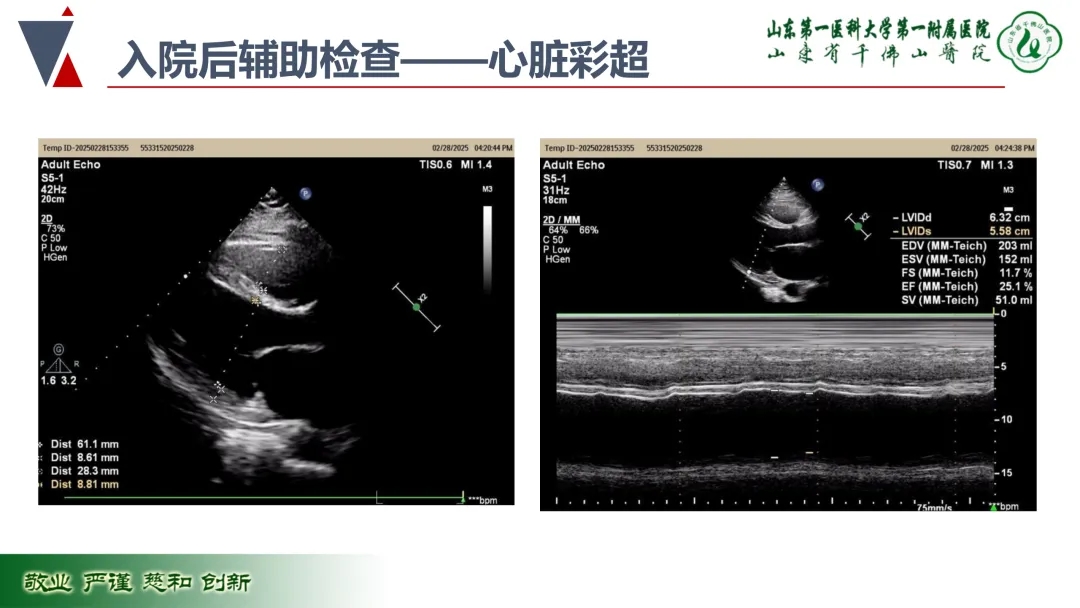

病例名称:1例中年重症心衰患者的诊治之路